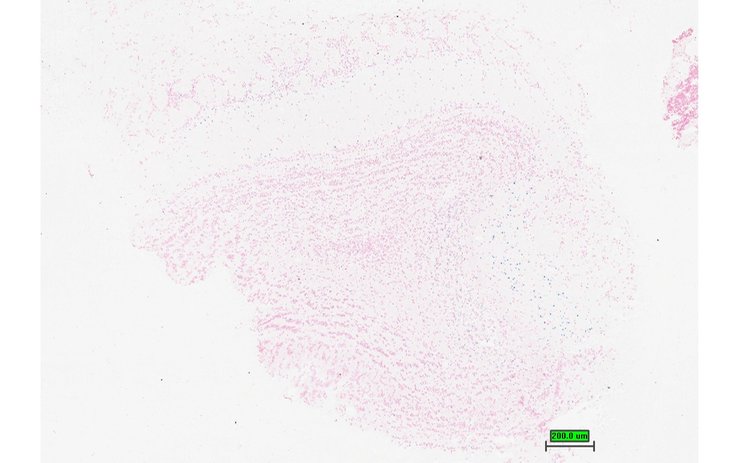

TS28: eye Present UC Davis_1856122

TS28: eye Present UC Davis_1856133

Specimen UC Davis_1856134: postnatal adult; Dzank1tm1b(KOMP)Wtsi/Dzank1+ (more )

TS28: eye Present UC Davis_1856134

TS28: eye Present UC Davis_1856135